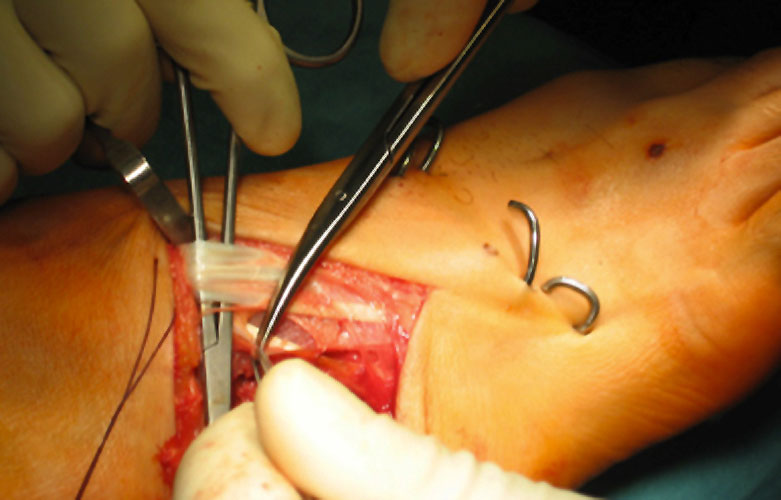

OP nach Steindler: Die verdickte und kontrakte Plantarfaszie wird komplett durchtrennt. Gelegentlich ist bei Kontraktur der Beugesehnen auch der calcaneare Ansatz des M. flexor digitorum brevis mit abzulösen. Dieser Eingriff steht zu Beginn der Hohlfußkorrektur. Der Zugang erfolgt über einen kleinen medialen Schnitt, über welchen sie die Plantarfaszie gut erreichen lässt (Abb. 23 und 24).

Zum Lesen der Bildbeschreibung und zur Vollansicht bitte die Bilder anklicken. Bilder: M. Walther